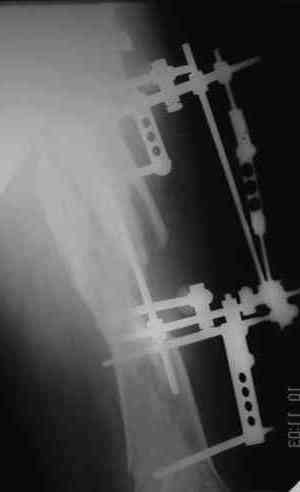

Уважаемые коллеги! Пришел на консультацию вот такой больной (первые 3-и рисунка). Травма автодорожная, апрель 2006г. Лечился консервативно, вытяжение и гипс. Через пять месяцев стал ходить. Укорочение бедра 6 см. 26 февраля 2007г. оступился, упал. Прооперирован в г.Баку - наложен стержневой аппарат. Ходит с костылями, наступая на левую ногу.

Мы попросили что нибудь из ранних снимков. Принес рентгенограммы перелома (рис. 4,5). Посмотрели, наснимали сами (рис. 6-10). Похоже, что нет сращения нигде. Хотелось - бы обсудить следующие вопросы: 1. дальнейшая тактика - реостеосинтез или подождать (ослабить аппарат, дать нагрузку и т.д.)? 2. если реостеосинтез - то чем и как? Юрий Алексеевич Булахтин